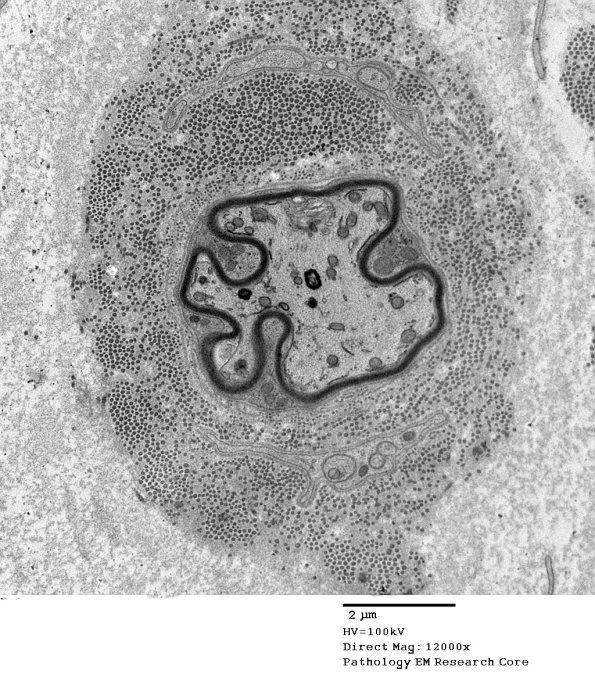

This thinly myelinated axon is found in the center of condensed collagen and matrix. (electron micrographs)